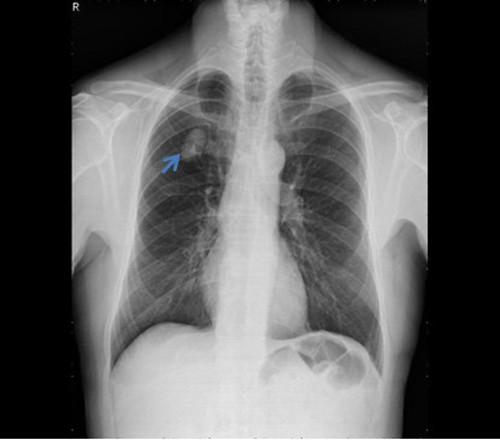

U phổi (mũi tên) trên hình chụp X-quang

Bác sĩ đã chỉ định chụp X-quang và CT ngực phát hiện bóng mờ đáy phổi trái. Khối u choán chỗ thùy dưới phổi trái, kích thước 25x27 mm.

Bác sĩ Thiện cho biết, khối u hình cầu, giới hạn rõ, không có vỏ bao, dễ bóc tách ra khỏi mô phổi xung quanh, mật độ chắc, mặt cắt trắng xám, có các khe nang chứa dịch dạng keo sệt, trong, không có vôi hóa, không có vùng xuất huyết, hoại tử.

Về vi thể, khối u chủ yếu gồm mô mỡ sợi, biểu mô hô hấp và mô sụn lành tính.